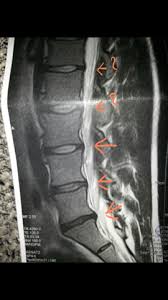

These levels were investigated in this study as degeneration occurs most often and earliest in these three lower vertebral levels 17 fourth and fifth lumbar spine vertebrae and the first sacral vertebra were evaluated for disc bulging and protrusion See Lumbar Artificial Disc Replacement for Chronic Back Pain A high intensity zone HIZ is seen at L4-L5 Depending on the extensiveness. Es wurde eine ausgeprägte Osteochondrose mit Pseudolisthese und Bandscheibenprotrusion L45 diagnostiziert. Bei einer Bandscheibenprotrusion können die Nervenwurzeln hier blau geschädigt werden.

Protrusion L4 5 Bandscheibenprotrusion L4 L5 Mrt Lws